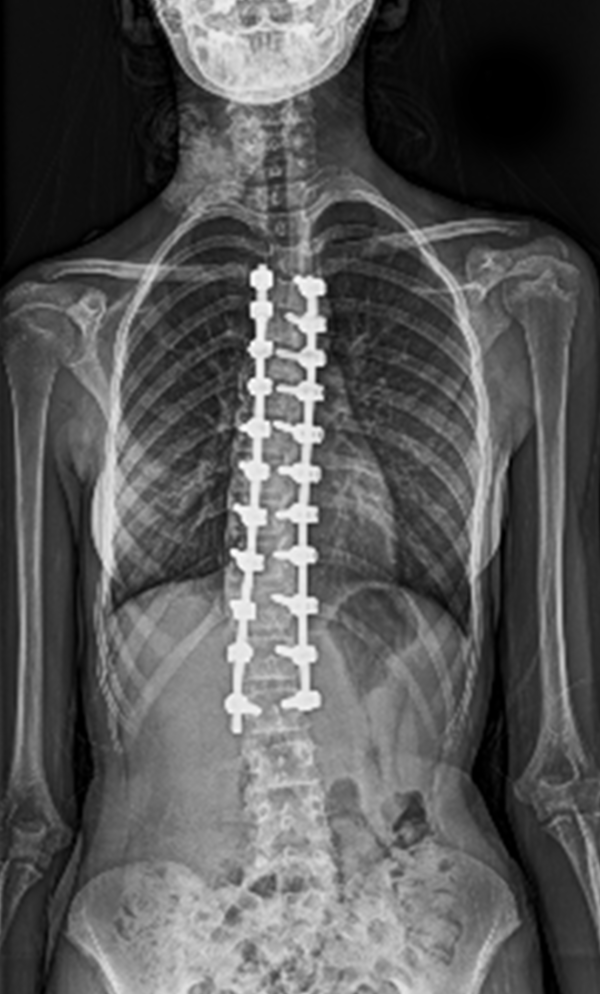

BEYOND RECOVERY : REAL STORIES

Gallery : Before - After